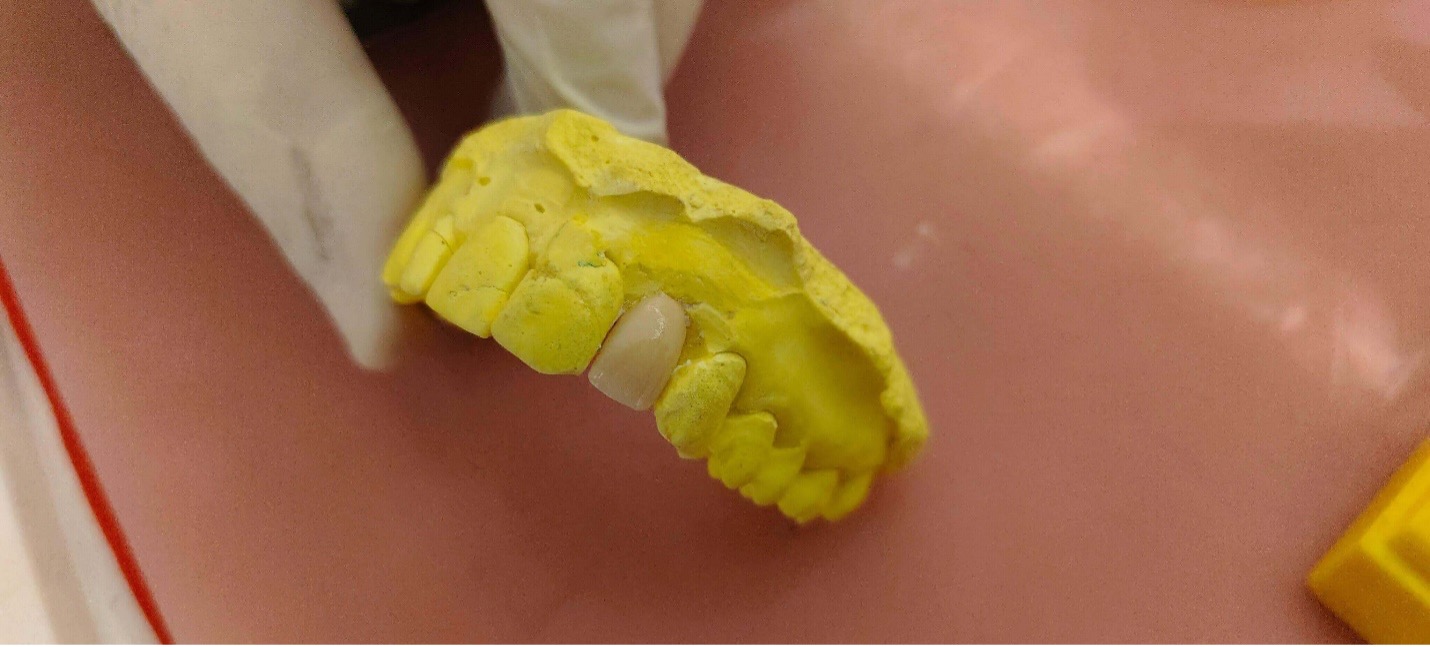

● After preparing and shaping the crown, the dentist take impressions of the teeth with either alginate or silicone putty materials

● Impressions can also be taken with the help of CAD CAM techniques which provides digital image of the teeth

● The impression is sent to the lab for manufacturing of the crown